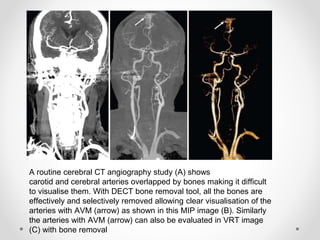

A routine cerebral CT angiography study (A) shows

carotid and cerebral arteries overlapped by bones making it difficult

to visualise them. With DECT bone removal tool, all the bones are

effectively and selectively removed allowing clear visualisation of the

arteries with AVM (arrow) as shown in this MIP image (B). Similarly

the arteries with AVM (arrow) can also be evaluated in VRT image

(C) with bone removal